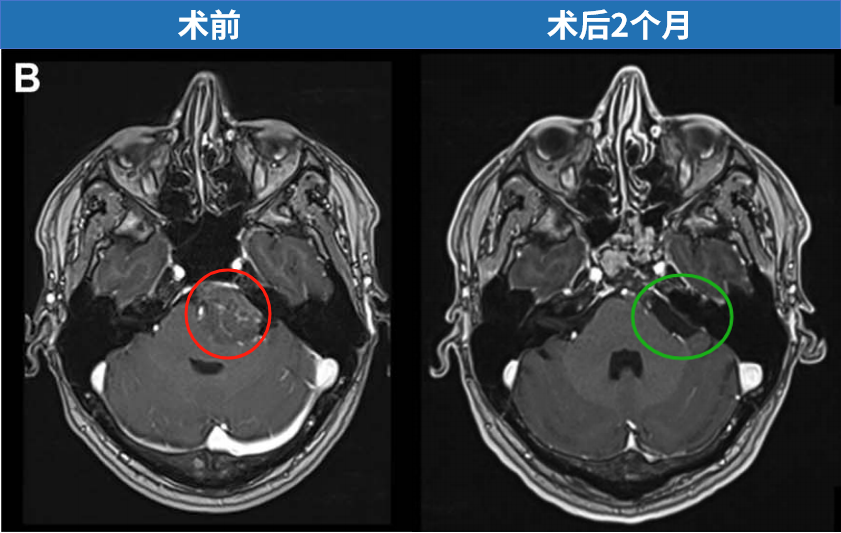

先来看看这个案例,29×39×38 mm,一个大型岩斜区脑膜瘤像一个小山丘一样,山顶直接挤压“生命禁区”脑干,还与神经血管结构紧密粘连。此时的他仅有头痛症状。

其实不然,在INC福教授的定制化手术策略之下,无需开颅,仅右侧单鼻孔入路便全切肿瘤。脑干复位良好,未见脑脊液漏及新发神经功能障碍。